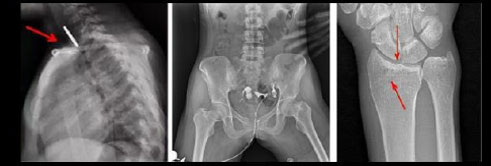

- Применяется в различных клинических рентгенологических исследованиях, таких как рентгенография, цифровая флюороскопия, контрастная и визуализированная точная съемка DR

- Функция Автоматического сшивания изображений, позволяющая формировать предоперационные хирургические планы и оценивать послеоперационные последствия, такие как сколиоз и нагрузка на костные ортопедические изделия, протезирование колена и эндопротезирование тазобедренного сустава (данная функция опциональна и предоставляется по предварительному запросу)

Рентгенологические исследования: рентгенография больших переломов костей и масштабное физическое рентгенографическое обследование, флюороскопия всех частей тела (грудная клетка, живот и т.д.), пищеводная ангиография, ангиография верхних отделов желудочно-кишечного тракта, полная ангиография желудочно-кишечного тракта, холангиография, Т-образная холангиография, ЭРХПГ, внутривенная пиелография, гистеросальпингография и т.д.